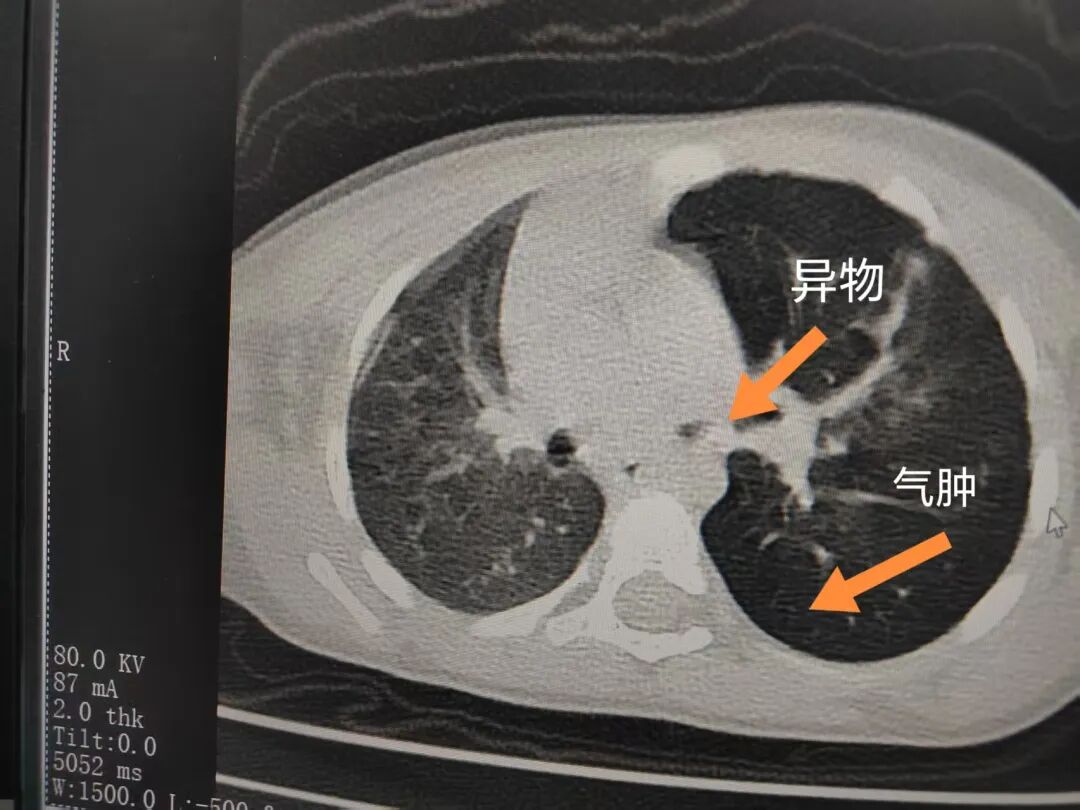

三天后(11月13日),趙寶出現(xiàn)高熱、咳喘加重,家長(zhǎng)著急了,再次帶他來(lái)到醫(yī)院。CT檢查顯示左肺過(guò)度充氣,左肺上下葉支氣管主干見(jiàn)不規(guī)則高密度影,左肺上葉可見(jiàn)大片狀密度增高影,縱隔窗實(shí)變,提示為“左側(cè)支氣管內(nèi)異物并繼發(fā)性改變,左肺上葉舌段肺膨脹不全”。

市二院小兒呼吸內(nèi)科副主任楊亞娟介紹,異物誤入氣道可能導(dǎo)致氣道阻塞,嚴(yán)重時(shí)可引發(fā)窒息,甚至危及生命。若異物進(jìn)入支氣管,造成不完全堵塞,可引起阻塞性肺氣腫;如完全堵塞支氣管,則可能導(dǎo)致肺組織萎縮,形成肺不張。此外,若異物存留時(shí)間較長(zhǎng),或?yàn)橹参镄援愇?,容易合并?xì)菌感染,產(chǎn)生膿性分泌物,進(jìn)而發(fā)展為肺炎。她強(qiáng)調(diào),盡早診斷并取出異物,是減少并發(fā)癥、降低病死率的關(guān)鍵。